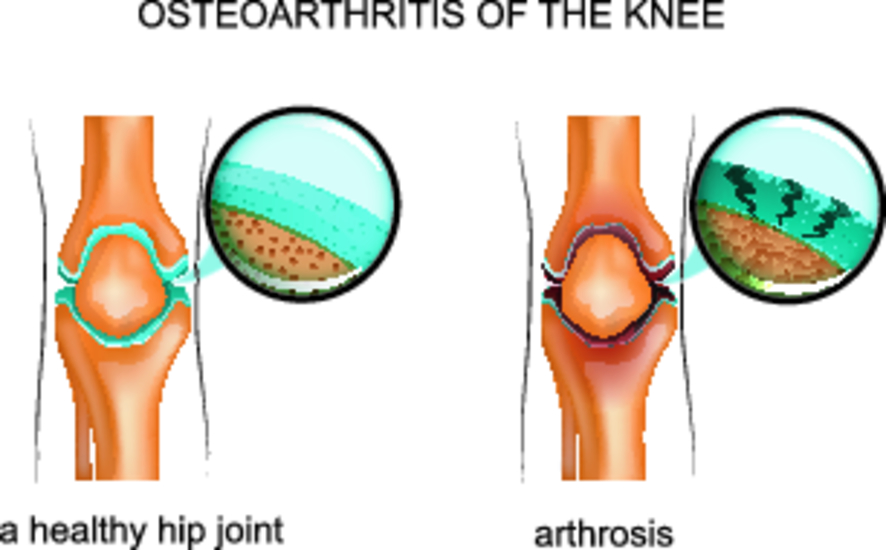

Причинные факторы остеоартроза запускают процессы раннего старения суставного хряща – замедляется обмен веществ в хрящевой ткани, в результате чего хрящ теряет эластичность, становится шероховатым, на нем появляются трещины, обнажая подлежащую кость.

Следствием сниженной амортизации становится уплотнение суставных поверхностей костей и образование кист, участков ишемии, склероза.

Благодаря компенсаторным процессам хрящ разрастается за пределы сустава, формируя краевые остеофиты.

Конечным результатом вышеописанных процессов является полное разрушение хряща и нарушение функции пораженного сустава.